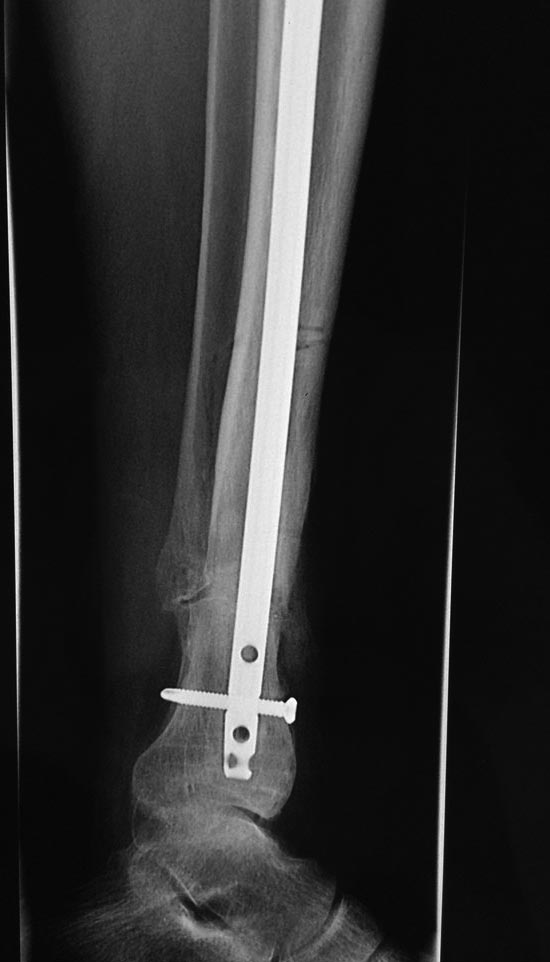

Уважаемые коллеги выразите Ваше мнение по следующему случаю.Молодой человек, 27 лет, находится на лечении с диагнозом: Ложный сустав большеберцовой кости в нижней трети, фиксированный интрамедуллярным блокированным стержнем (12.02.2014 г), ложный сустав малоберцовой кости в нижней трети левой голени, посттравматический артроз левого голеностопного сустава 1 стадии. Укорочение левой нижней конечности на 1,0 см. Со слов пациента известно, что в детстве получил перелом большеберцовой кости, лечился консервативно, перелом сросся с деформацией. Травма в июле 2010 г. бытовая-упал на лестнице, получил перелом малоберцовой кости, и перелом большеберцовой кости без смещения. Выполнена операция: Остеотомия большеберцовой кости в нижней трети, интрамедуллярный блокированный остеосинтез большеберцовой кости левой голени. Гладкое течение послеоперационного периода. Перелом большеберцовой кости сросся. Функция конечности восстановилась. В июне 2013 г выполнена операция удаление интрамедуллярного стержня из большеберцовой кости левой голени. Гладкое течение послеоперационного периода. Приступил к занятием физкультурой, бег. В августе 2013 г спрыгнул с автобуса, с чемоданом в руках, появилась резкая боль в левой голени. За медицинской помощью обратился через 7 дней, при обследовании выявлено: Рефрактура большеберцовой кости. Рекомендовано консервативное лечение в гипсовой повязке. В январе 2014 г. установлен диагноз: Ложный сустав большеберцовой кости в нижней трети, малоберцовой кости в нижней трети левой голени. Контрактура сгибательно - разгибательная левого голеностопного сустава. Посттравматический артроз левого голеностопного сустава 1 стадии. Укорочение левой нижней конечности на 1,0 см. В феврале 2014 г выполнил первым этапом: Фиксацию ложного сустава в АНФ с восстановлением осей сегментов. Через семь дней БИОС с рассверливанием. После операции - вальгус голеностопного сустава. Гладкое течение послеоперационного периода. Нагрузка по переносимости боли. Через 6 недель динамизация, через 2 недели стали мигрировать 2 фронтальных винта. Пытался подкрутить, пришлось удалить. Через 6 мес., контроль - линия ложного сустава прослеживается, но имеется периостальная костная мозоль. Не хватает стабильности.Вопрос что делать?Вариант № 1- выполнить реостеосинтез с рассверливанием КМК и на 12 мм диаметра гвоздь (стоит 11 мм)и убрать ротацию стопы руками одномоментно или одномоментно при помощи АНФ во время операции. Вариант № 2 выполнить удаление гвоздя, сделать все то же, что 6 месяцев назад, но с восстановлением анатомических взаимоотношений в голеностопном суставе.Вариант № 3 Двухэтапно, вторым этапом пластина на большеберцовую кость + костная пластика области не сращения.Вариант № 4 удаление гвоздя и лечение в КДА. Вопросы:1. Какой вариант оперативного лечения будет оптимальным в данном случае.2. При двухэтапной методике в дистальном отломке имеется канал от гвоздя, как направить гвоздь к наружному отделу дистального отломка большеберцовой кости. Есть опасения, что гвоздик может пойти по тому же каналу. Использовать поллер спицы или винты – сработают ли? И достаточна ли будет жесткость фиксации дистального отломка большеберцовой кости на гвоздике при 3 – 4 винтах при реостеосинтезе гвоздем.3. Нужен ли остеосинтез малоберцовой кости в нижней трети, с целью создания латеральной опоры. К сообществу за советом.

Александр Николаевич спасибо за ответ. Три снимка перед внешним видом конечности крайние. На одном из них левая стопа в положении внутренней ротации 15 градусов.